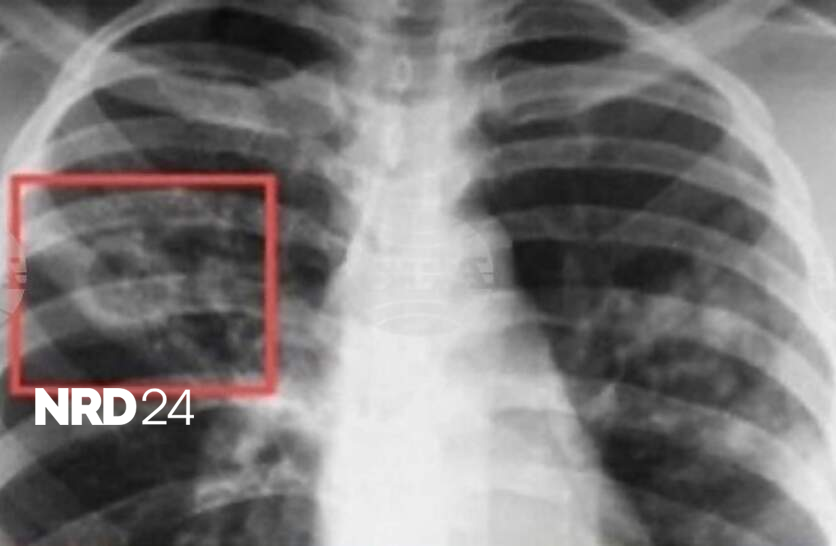

Безплатни профилактични прегледи за риск от туберкулоза ще извършват от днес, 15 септември, до петък в "Специализирана болница за активно лечение на пневмо-фтизиатрични заболявания – д-р Н. Пенчев“ - Пазарджик, съобщиха от местната администрация. Кампанията е част от изпълнението на Националната програма за превенция и контрол на туберкулозата в Република България за периода 2021 – 2025 г. По време на „Седмицата на отворените врати“ всеки желаещ ще може да премине скрининг за риск от туберкулоза чрез анкета и медицинска консултация. При установяване на риск, ще бъдат извършени допълнителни прегледи и изследвания. През юни в същата болница бе проведена Седмица на отворените врати, в която пациентите имаха безплатен достъп до скринингови прегледи за туберкулоза.